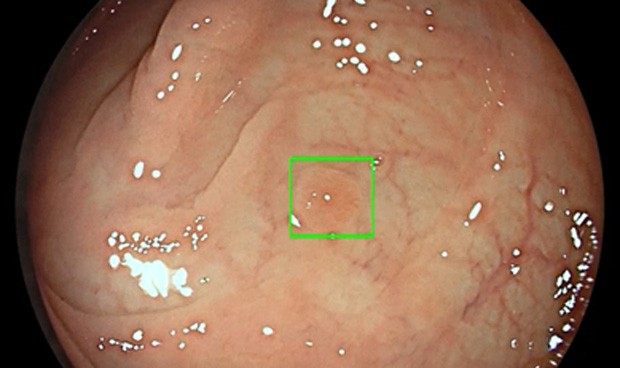

GI Genius utiliza IA avanzada para señalar la presencia de lesiones precancerosas con un marcador visual en tiempo real

Unidad de endoscopia inteligente GI Genius.

GI Genius utiliza inteligencia artificial avanzada para señalar la presencia de lesiones precancerosas con un marcador visual en tiempo real, y funciona como un segundo observador siempre atento. Los estudios han demostrado que con un segundo observador se pueden incrementar las tasas de detección de pólipos; por cada punto porcentual de aumento de la tasa de detección de adenomas, se reduce un 3 por ciento el riesgo de cáncer colorrectal.

"El módulo GI Genius detecta los pólipos automáticamente, incluso pequeños pólipos planos que pueden pasar desapercibidos, aumentando así la precisión y reduciendo el riesgo de cánceres de intervalo, que se pueden producir entre colonoscopias", declara Di Napoli.